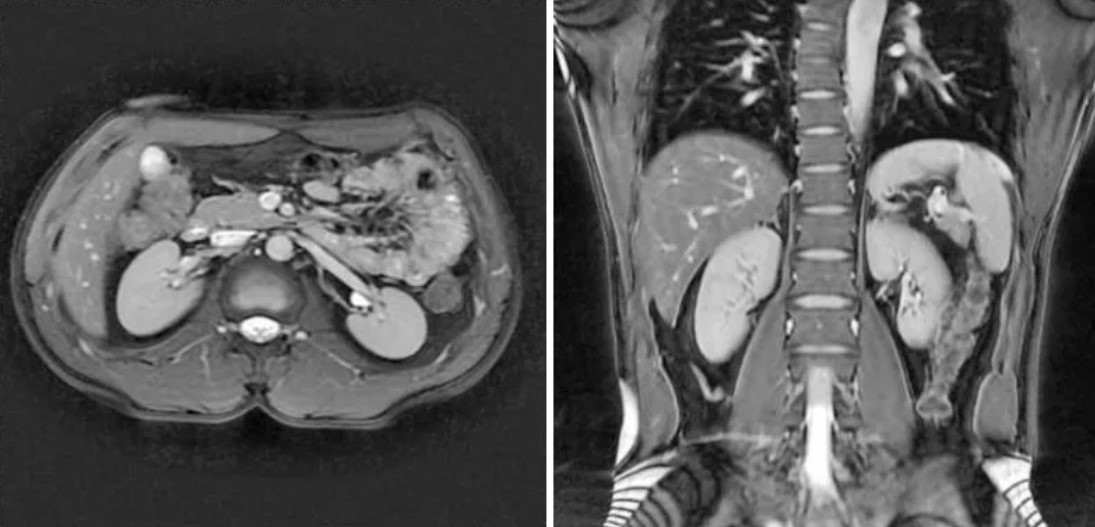

Как выглядит нормальное МРТ почек

Пациенты, получившие на руки заключение МРТ, часто сталкиваются с непониманием используемых формулировок и терминов. Важно знать, как выглядит нормальная картина, чтобы не переживать из-за стандартных формулировок. В описании нормального МРТ почек обычно указывается, что органы расположены типично, имеют обычную форму и размеры, симметричны, паренхима равномерной структуры и интенсивности сигнала, без очаговых изменений. Также должно быть указано, что чашечно-лоханочная система не расширена, мочеточники не визуализируются – что в норме, если они не патологически изменены.

Фраза «патологических изменений не выявлено» или «МР-картина без особенностей» означает, что снимки не содержат признаков заболеваний. Если в заключении указано наличие физиологически расположенного жира, отдельных мелких кист до 2-3 мм, это, как правило, не считается патологией и не требует лечения. Отдельные фразы могут показаться тревожными, но они могут лишь указывать на индивидуальные анатомические особенности.

Важно помнить, что интерпретация даже нормального результата требует клинической оценки. Только врач, который направил на обследование, сможет соотнести полученные данные с жалобами и анамнезом. Однако знание того, как выглядит нормальное МРТ почек, позволяет пациенту чувствовать себя увереннее и не делать поспешных выводов при чтении заключения.